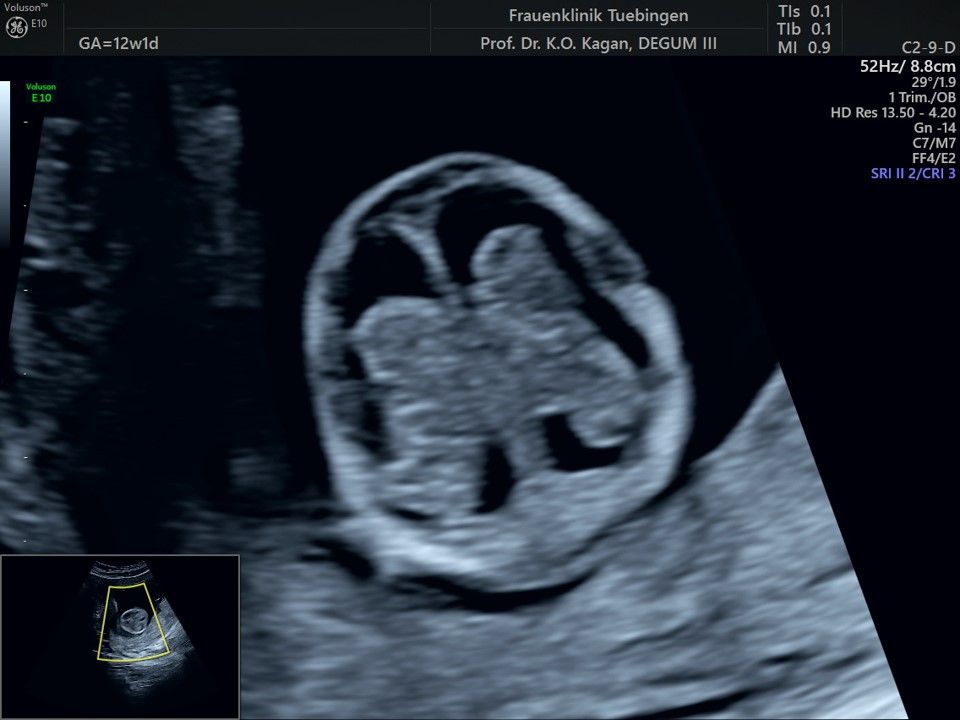

Im Rahmen des Ersttrimester-Screenings untersuchen wir die Organe des Feten mittels Ultraschall. Dabei machen wir auch gerne ein Bild für Sie.

Obwohl der Fet zu diesem Zeitpunkt erst zwischen 5 und 8cm groß ist, lassen sich bereits etwa die Hälfte aller schwerwiegenden Fehlbildungen erkennen bzw. ausschließen. Sollten wir eine Auffälligkeit sehen, werden wir mit Ihnen den Befund und das weitere Vorgehen ausführlich besprechen.

Herz